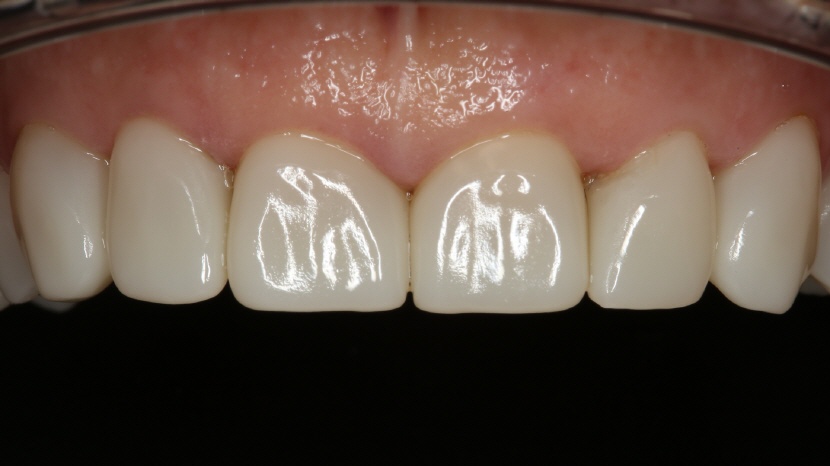

• Oberkiefer Front:

Wie alle Cerec-Rekonstruktionen wurden ebenfalls die Frontzahnkronen in einer Sitzung hergestellt, poliert und mit lichthärtendem Komposit (GC G-Aenial Universal Injectable A1) eingesetzt.